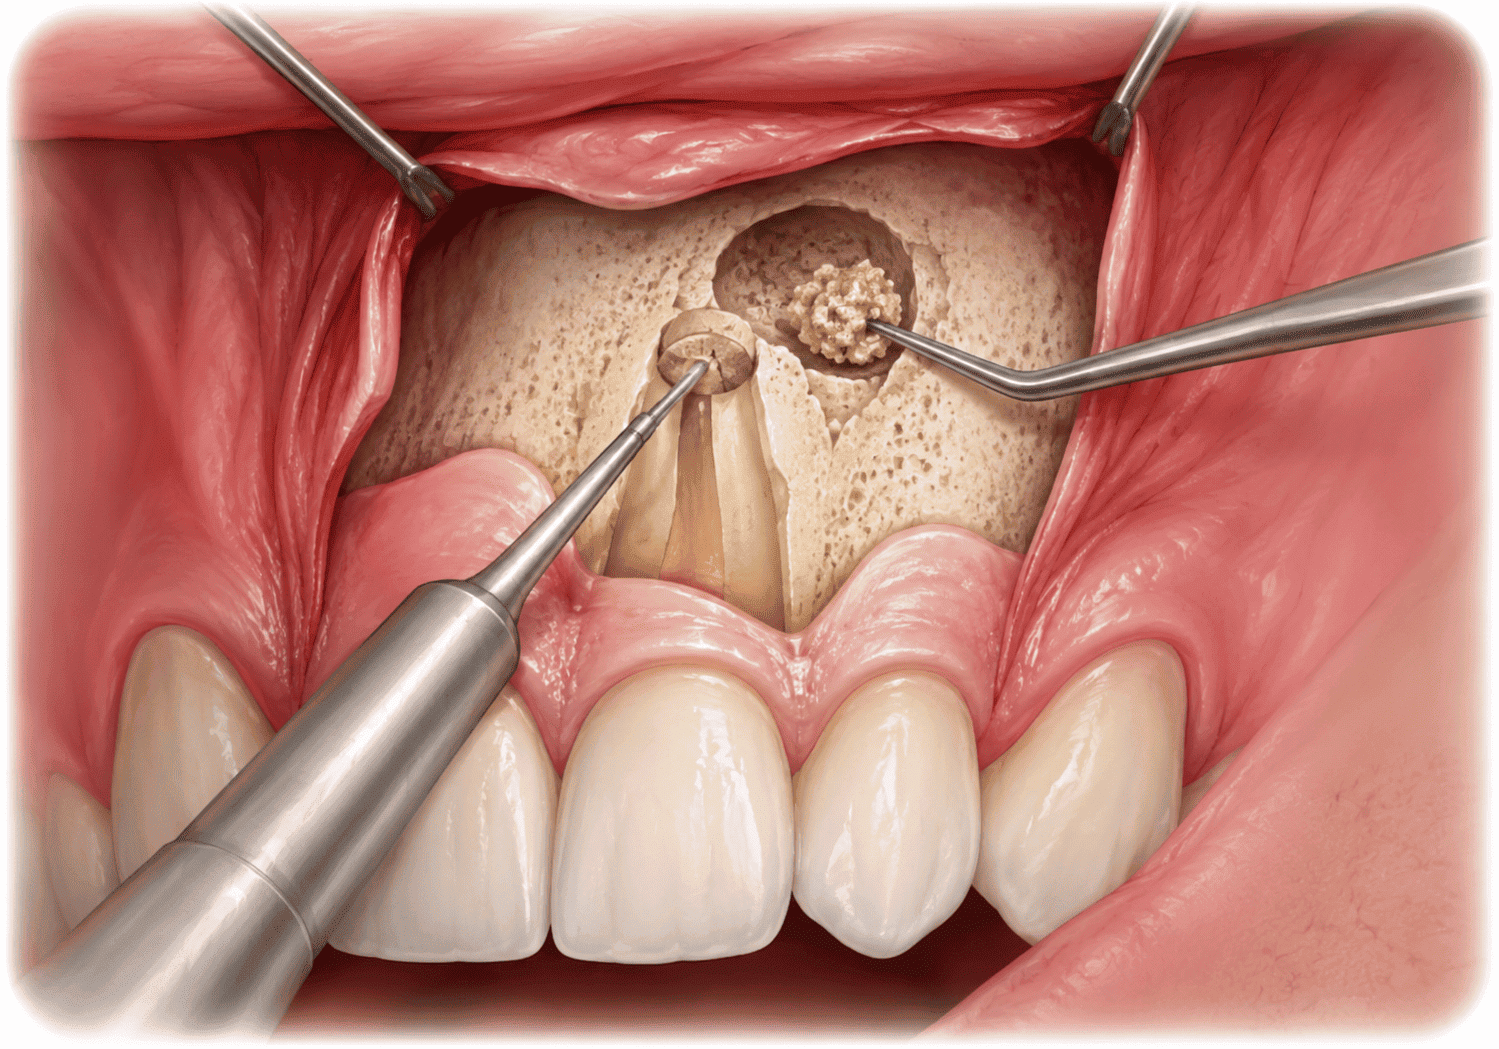

পেরিআপিক্যাল সার্জারি (Periapical Surgeries: Apicoectomy, Curettage)